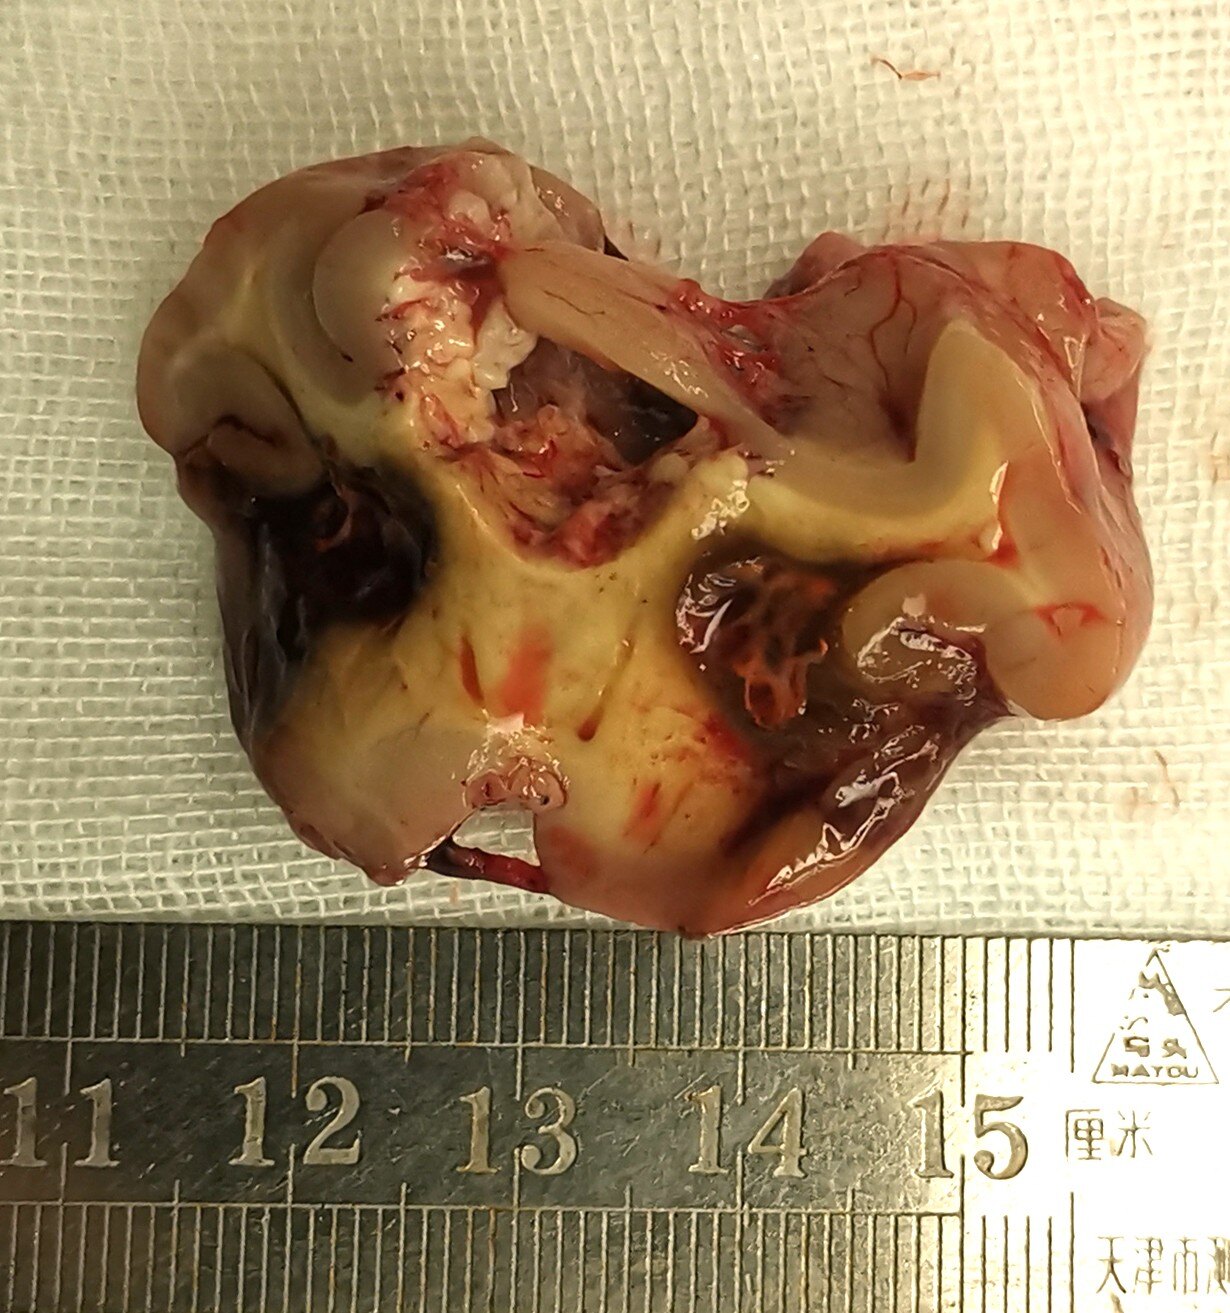

结果:患者行颞叶海绵状血管瘤切除术,及部分瘤周含铁血黄素沉着脑组织切除,术后口服卡马西平,每天400毫克,术后无发作,6个月后停抗癫痫药物,目前已经随访2年余,无癫痫发作。

海绵状血管瘤是由众多薄壁血管组成的海绵状异常血管团,外观呈紫红色,并非真性肿瘤,按组织学分类属于脑血管畸形,这些畸形血管紧密相贴,血管间没有或极少有脑实质组织。